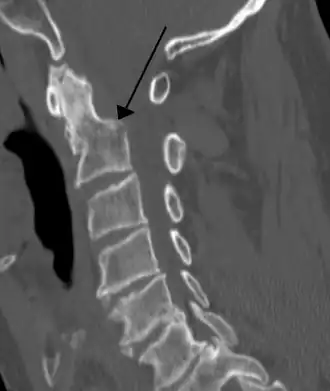

![]() Спиральная компьютерная томограмма перелома основания зубовидного отростка (тип II) со смещением | |

- При типе II (более 60 %) линия перелома расположена на границе зубовидного отростка и тела позвонка[2].

Диагностика заболевания включает наличие клинической симптоматики, данных пальпации, рентгенографии в 2-х проекциях (боковой и прямой через открытый рот) и компьютерной томографии. На снимках могут определяться линия перелома, наличие смещения, а также увеличение тени превертебральной ткани на уровне переднего бугорка атланта[4].